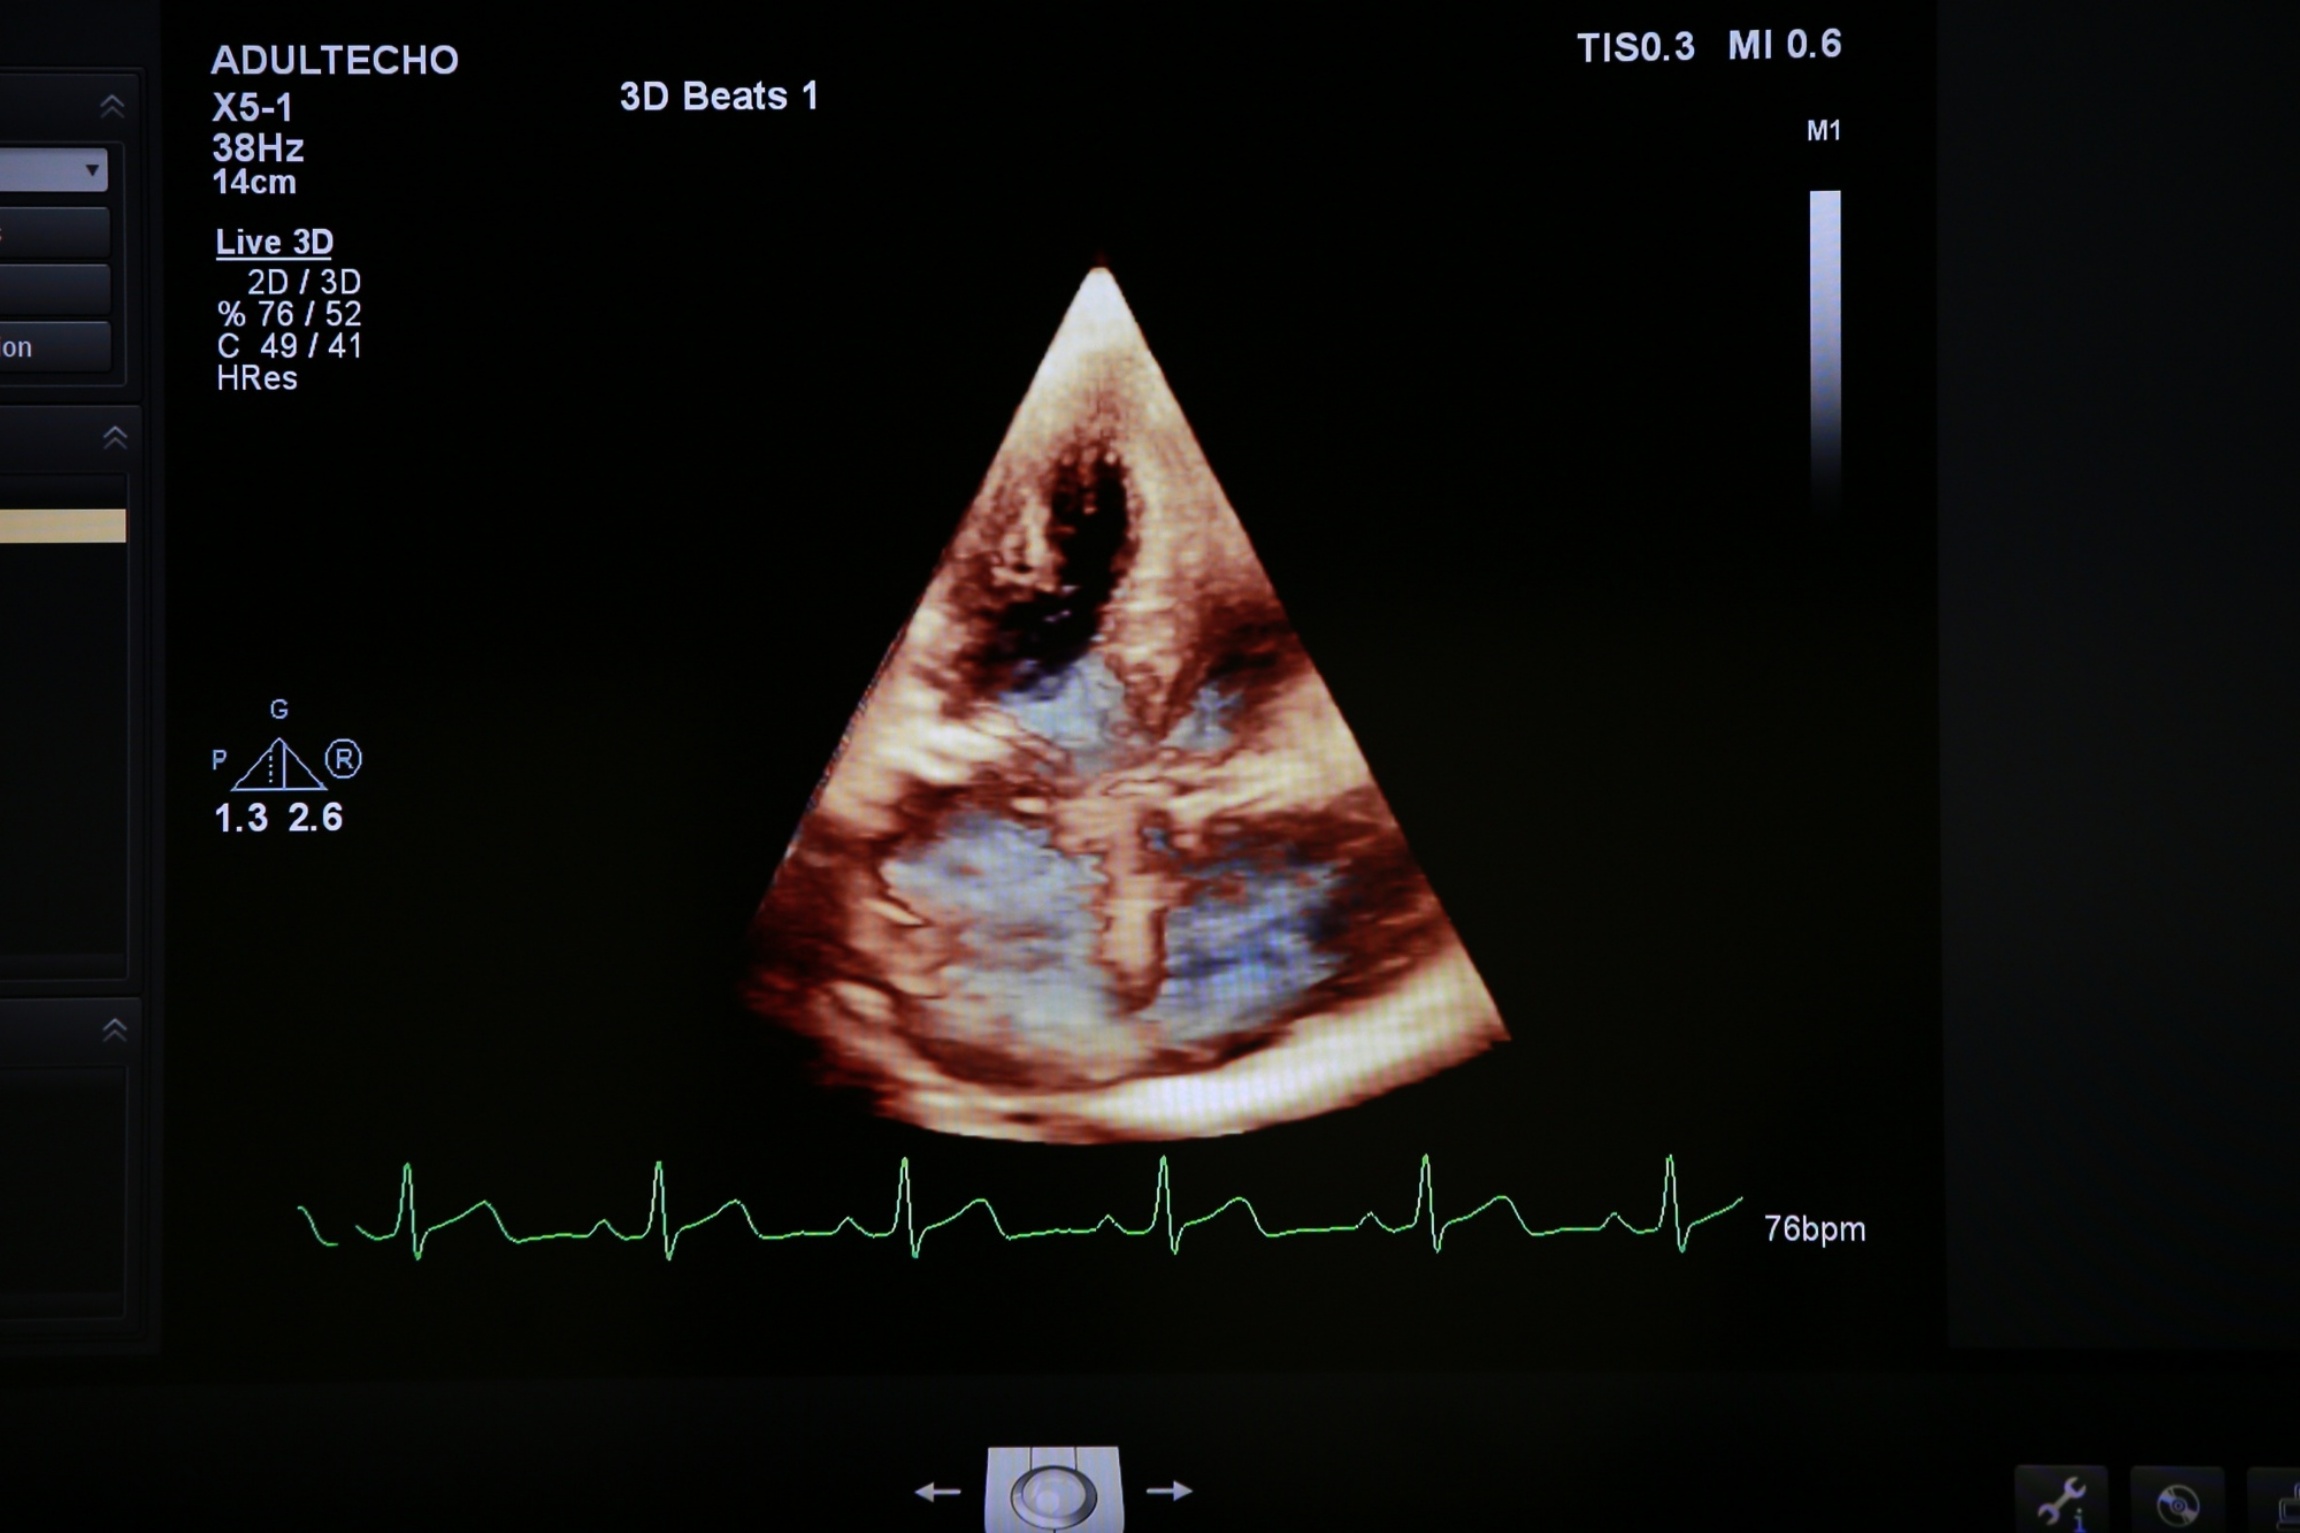

“การซักประวัติ ตรวจร่างกาย และการใช้หูฟังฟังเสียงหัวใจของแพทย์เป็นวิธีการนำมาซึ่งการวินิจฉัยโรคหัวใจที่ดี แต่บ่อยครั้งอาจไม่เพียงพอ ต้องอาศัยการตรวจเพิ่มเติมที่ละเอียดมากขึ้น ปัจจุบันมีการตรวจเพิ่มเติมทางด้านหัวใจหลายประเภท และมีจุดเด่นและข้อจำกัดแตกต่างกัน ดังนั้น ผู้ป่วยบางรายอาจต้องได้รับการตรวจเพิ่มเติมมากกว่าหนึ่งชนิด เช่น การตรวจคลื่นไฟฟ้าหัวใจหรือ EKG; การตรวจวิ่งสายพานหรือ Stress Test; การตรวจทางภาพถ่ายรังสีแบบธรรมดา จนถึง เอ็กซ์เรย์คอมพิวเตอร์ หรือ เอ็กซเรย์คลื่นแม่เหล็กไฟฟ้า หรือ CT scan cardiac MRI; การฉีดสีหลอดเลือดหัวใจ และการตรวจที่จัดได้ว่าเป็นหนึ่งในการตรวจที่สำคัญที่สุด คือ การตรวจด้วยคลื่นเสียงสะท้อนหัวใจขั้นสูง (Echocardiography)” รศ.พญ.ศริญญา อธิบายเพิ่มเติม